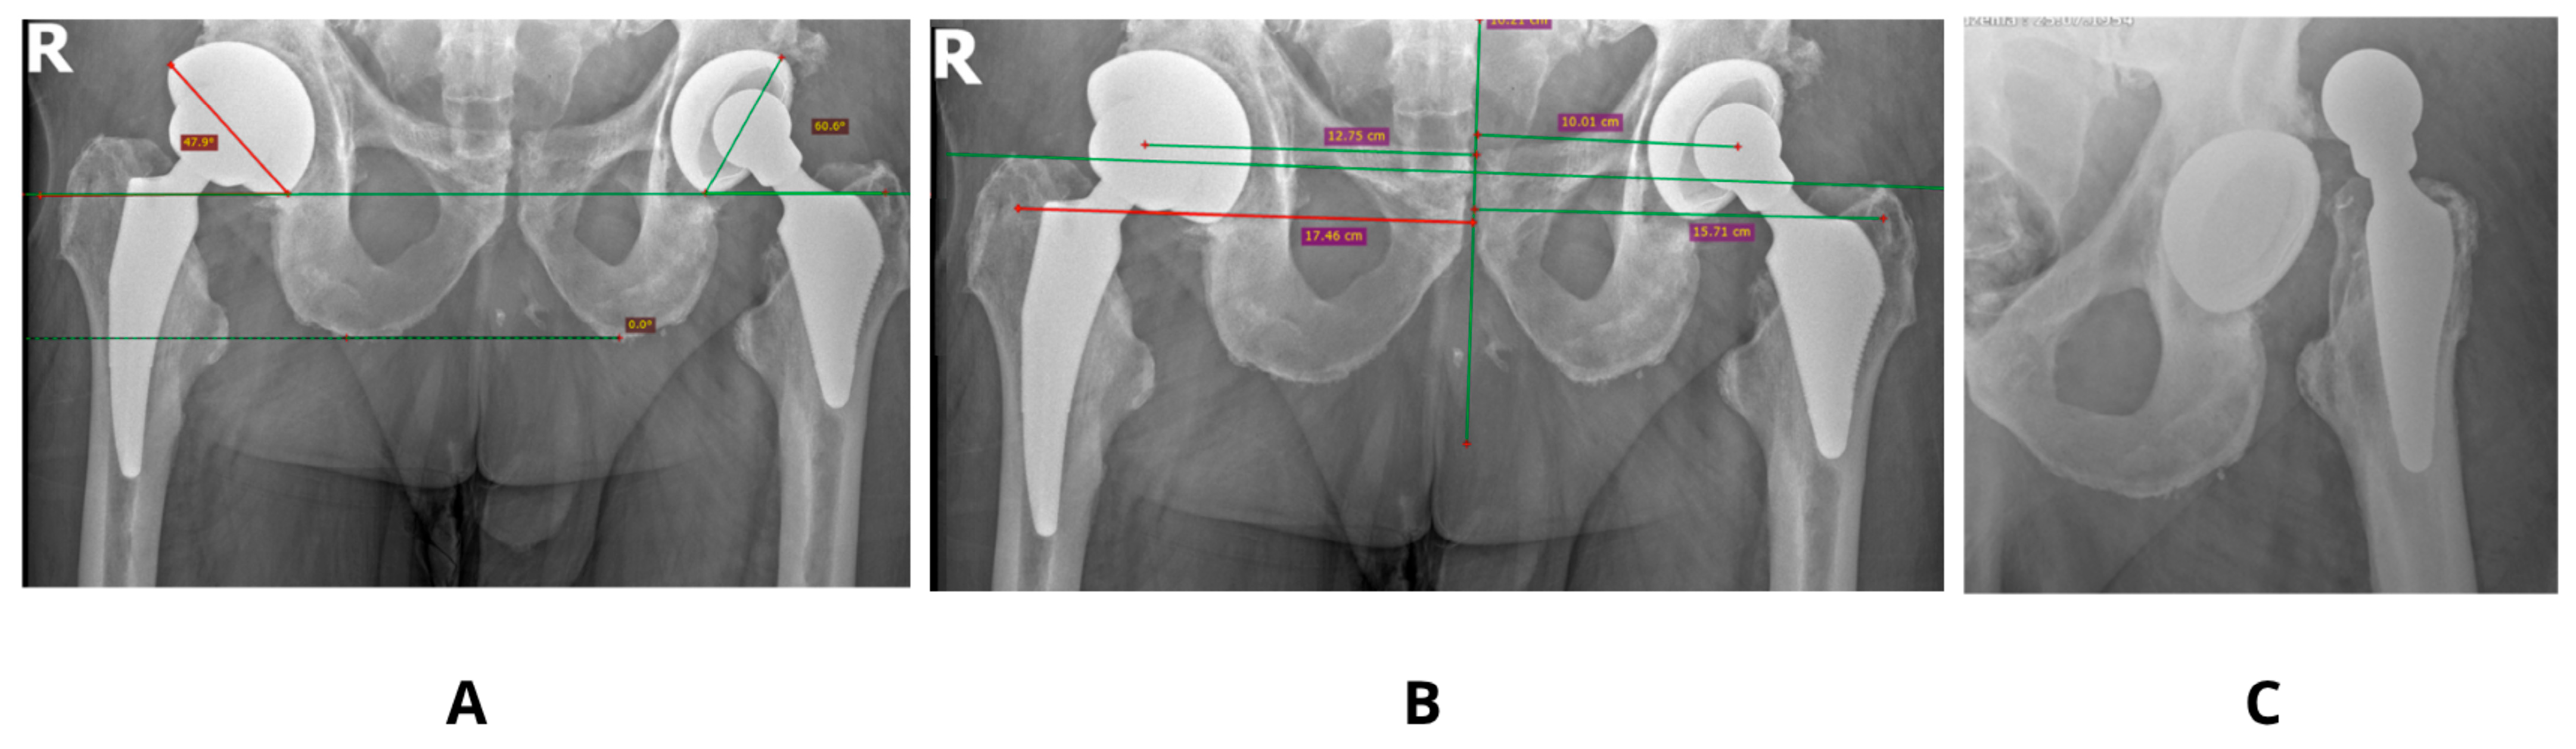

Figure 5. An example of an implant inserted with 0° anteversion of the acetabulum—(A), and its dislocation—(B).

Patient-specific factors, including pelvic tilt and femoral morphology (e.g., neck-shaft angle, femoral version, and offset), substantially influence prosthetic component orientation and joint stability. Prior research by Yang et al. [18] demonstrated that minor alterations in pelvic tilt (5–10°) can significantly impact functional anteversion, increasing the risk of prosthetic impingement or dislocation [Figure 5].